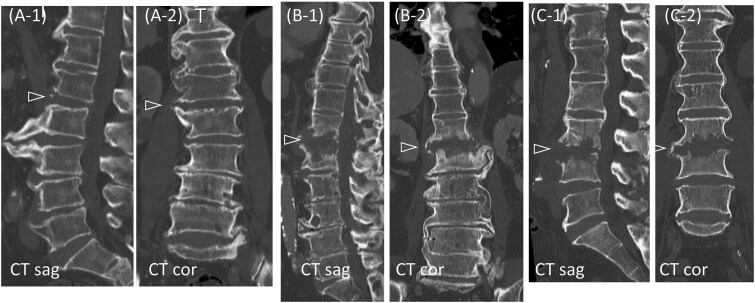

化脓性脊柱炎和弥漫性特发性骨骼肥厚症(DISH)都可以发生在老年人的胸腰椎。在化脓性脊柱炎患者中,据报道,DISH患者的死亡率明显高于非DISH患者。然而,死亡率增加的原因和预防致命后果的有效战略仍有待确定。在这里,我们报告三例化脓性脊柱炎影响非强直性病变的老年DISH患者。这些患者成功地使用穿透性终板螺钉进行前后固定,提供牢固的固定,在DISH中特别有利。对于伴有非强直性病变的化脓性脊柱炎患者,在计算机断层扫描和磁共振成像的指导下,采用穿透性终板螺钉进行早期脊柱固定,可能有助于防止老年患者卧床不起。

Both pyogenic spondylitis and diffuse idiopathic skeletal hyperostosis (DISH) can develop in the thoracolumbar spine of older adults. Among patients with pyogenic spondylitis, those with DISH reportedly have a significantly higher mortality rate than those without DISH. However, the reasons for this increased mortality and effective strategies for preventing fatal outcomes remain to be determined. Here, we report three cases of pyogenic spondylitis affecting non-ankylotic lesions in older patients with DISH. These patients were successfully treated with anterior and posterior fixation using penetrating endplate screws, which provide strong fixation and are particularly advantageous in DISH. In cases of pyogenic spondylitis involving non-ankylotic lesions in DISH, early spinal fixation with penetrating endplate screws, guided using computed tomography and magnetic resonance imaging, may help prevent older adult patients from becoming bedridden.